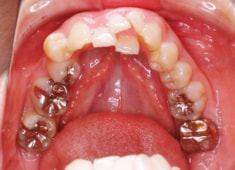

治療後(3年2ヶ月後)